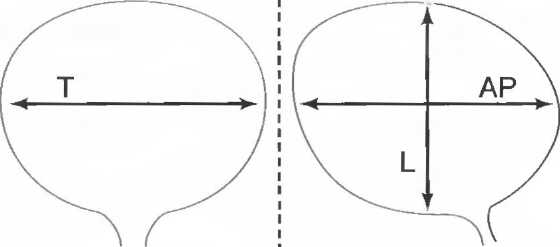

Форма среза, получаемая при использовании различных датчиков

1. Линейный датчик. Срезы при использовании таких датчиков имеют форму прямоугольников. Эти датчики наиболее удобны в акушерских исследованиях, а также при исследовании щитовидной и молочных желез (рис. 7а).

Рис.7а. Срезы прямоугольной формы, получаемые при использовании линейного датчика.

2. Секторный датчик. Срезы имеют форму веера, почти треугольного. Эти датчики удобно использовать при наличии очень небольшого по площади, доступного для исследования пространства. Они используются для исследования верхних отделов брюшной полости, а также в гинекологии и кардиологии (рис. 76).

Рис.7б. Срезы в форме веера, получаемые при использовании секторного датчика.

3. Конвексный датчик. Получаемый срез имеет форму, промежуточную между формой среза линейного и секторного датчиков, и используется для сканирования всех частей тела, кроме эхокардиографии (рис. 7в).

Рис.7в. Широкополосный веерообразный срез с широкой, изогнутой вершиной отконвексного датчика.